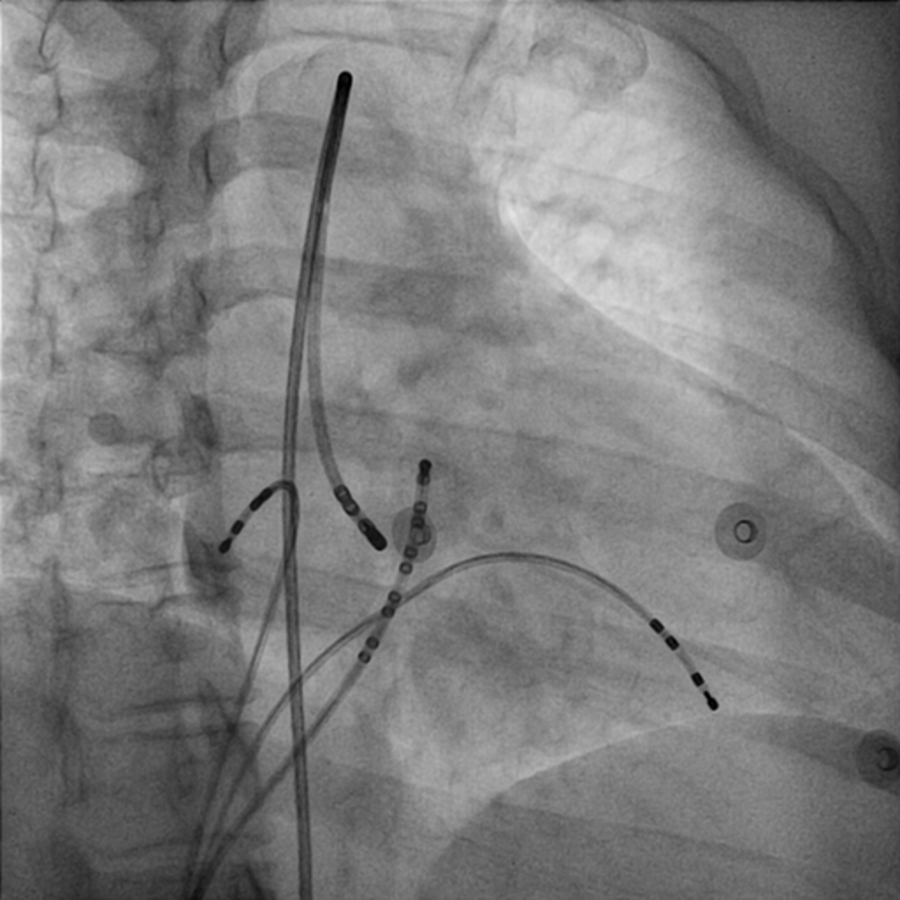

Single ventricular extrastimulus

02_rv_600_300.jpg